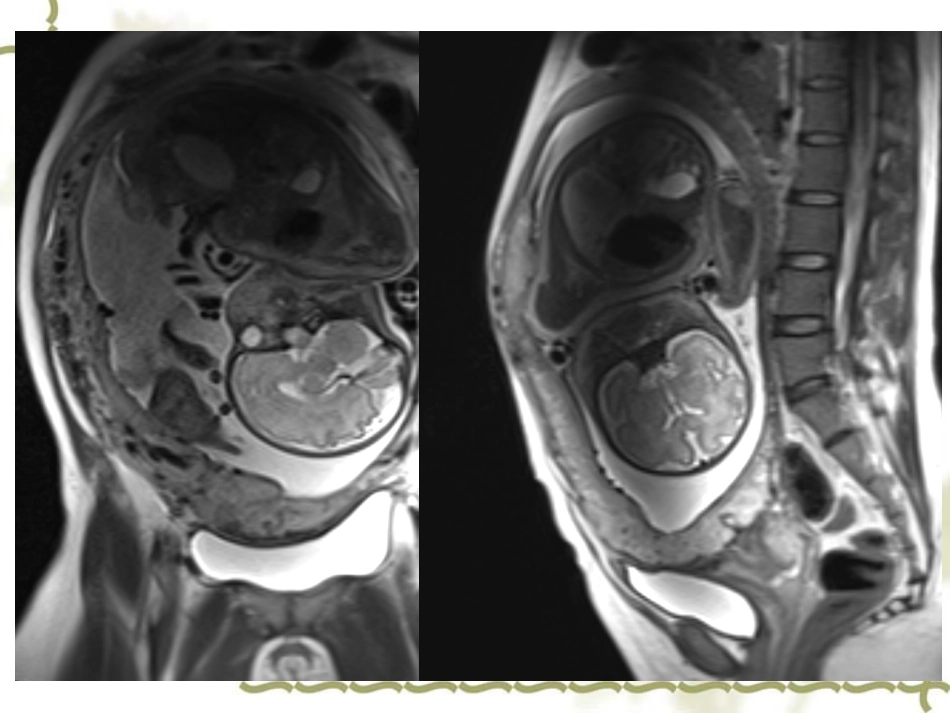

早会随访(2014-08-15)福建医科大学附属第一医院刘颖Case37岁,女性,停经32周,反复阴道流血1月余。2003年当地医院行剖宫产术。您的诊断?前置胎盘类型?是否植入?超声宫内单活胎,晚孕(横位)前置胎盘(中央性)子宫前壁下段(剖腹产切口周围)胎盘组织达浆膜层术中所见检查见胎盘大部分位于子宫前壁下段并折后子宫后壁并完全覆盖宫颈内口。上段胎盘剥离较顺利,前后壁下段胎盘剥离困难,部分植入于子宫前后壁。病理(胎盘)送检妊娠晚期胎盘,胎盘母体面小叶分隔欠清,胎盘各级绒毛干分枝结构尚正常,局部区域查见血肿、梗死及钙化,绒毛微血管基底膜增厚,部分玻璃样变性及个别玻璃样小球形成,部分区域见合体滋养叶细胞结节增多,请结合临床。前置胎盘胎盘植入MRI肠管蠕动及胎动的运动伪影重,孕妇难以坚持是胎盘及胎儿MRI检查的难点;孕妇平卧,为减少子宫对腹盆腔血管的压迫,还可左侧卧位;快速成像序列;矢状位,非抑脂T2WI。序列的选择HASTETrufi序列的选择VIBEMRI清晰显示胎盘位置,胎儿先露部;测量胎盘大小、厚度;评估子宫内膜的厚度、完整度。增强MRI识别植入深度,鉴别产后胎盘滞留与胎盘植入。钆剂在胎儿体内的循环模式复杂,钆剂经尿液排入羊水后会再吞入,经肠道吸收,半衰期不详,有可能会造成不良影响特别是对于胎儿的肾损伤。胎盘妊娠12周形成,此时胎盘尚未成熟,T2WI呈均匀一致稍高信号。随胎龄增加,出现愈来愈多类圆形胎盘小叶。胎盘MR信号清晰显示胎盘位置、形态及胎盘内部三层结构:(1)胎盘绒毛膜板:表现为胎盘胎儿面的线状低信号,随胎龄增加,胎儿面绒毛切迹不断增多、加深,呈锯齿状。孕20周孕32周胎盘MR信号(2)胎盘实质:随着胎盘逐渐地成熟,胎盘实质内胎盘小叶不断增多,T2WI表现为类圆形高信号。孕20周孕32周胎盘MR信号(3)胎盘基底膜:随孕周增加,基底膜形成胎盘隔,MRI表现为自基底部向胎儿面的T2低信号分隔,未达绒毛板,相邻绒毛间隙融合,出现低信号的局灶性纤维化及钙化斑点孕20周孕32周胎盘位置随着孕周的增加胎盘位置将上升、远离宫颈内口。机制:(1)附着于宫体部的绒毛膜由于血供丰富,生长迅速。(2)随着孕周的增加,子宫下段延伸,这也使得胎盘远离宫颈内口。前置胎盘胎盘正常附着于子宫体部的前壁、后壁和侧壁,位置高于胎先露部。如果胎盘附着于子宫下端,位置低于胎先露部,就称为前置胎盘临床症状孕中、晚期无诱因、无痛性反复阴道流血。原因:子宫下段形成过程中,附着于该处的胎盘由于不能相应地延伸而剥离,结果血窦出血,表现为无痛性阴道流血。前置胎盘VS胎盘前置状态20周开始观察胎盘位置孕20-28周,胎盘附着于子宫下端,位置低于胎先露部,称胎盘前置状态。上述情况发生在孕28周后,称前置胎盘。停经25+5周,阴道流血2天前置胎盘(1)完全性前置胎盘:又称中央性前置胎盘,宫颈内口完全被胎盘组织所覆盖。(2)部分性前置胎盘:只有部分宫颈内口被胎盘组织覆盖。(3)边缘性前置胎盘:胎盘边缘达到或接近宫颈内口,但未覆盖宫颈内口。(4)低置胎盘:胎盘位于子宫下段,与宫颈内口有一定的距离。(无需剖宫)完全性前置胎盘完全性前置胎盘部分性前置胎盘边缘性前置胎盘确定胎盘边缘与宫颈内口的距离胎盘覆盖宫颈内口,测量胎盘边缘越过宫颈内口的距离。胎盘边缘未达宫颈内口,测定胎盘边缘与宫颈内口的距离。胎盘边缘距离宫颈内口超2cm,无需剖宫产。胎盘边缘距离宫颈内口2cm作为区别边缘性前置胎盘和低置胎盘的标准。胎盘植入前置胎盘孕妇胎盘植入的发生率为9%,无前置胎盘孕妇胎盘植入的发生率则为0.004%。胎盘绒毛侵入子宫肌层。胎盘植入可引起产后大出血及相关并发症,甚至导致产妇死亡,因此准确并提早诊断尤其重要。胎盘植入根据胎盘绒毛侵入子宫肌层的程度分3类:①胎盘粘连:胎盘绒毛侵入到肌层表面;②胎盘植入:胎盘绒毛侵入到肌层深部;③胎盘穿通:胎盘绒毛侵入子宫浆膜层甚至穿透浆膜层至膀胱、直肠等毗邻器官。胎盘粘连胎盘粘连胎盘植入子宫局限性膨隆表面血管扩张胎盘穿通胎盘位于子宫前壁,下方完全覆盖宫颈...